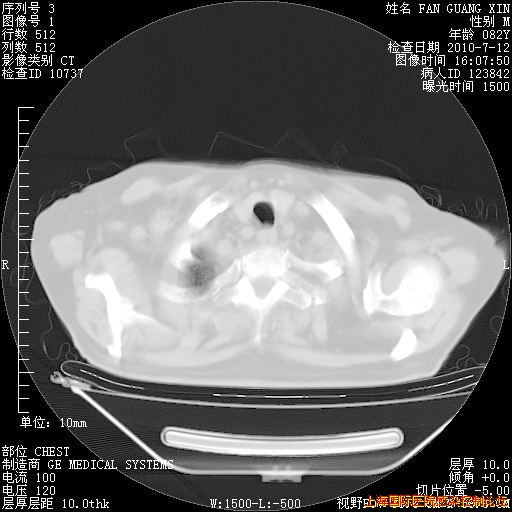

6月12日纵膈窗